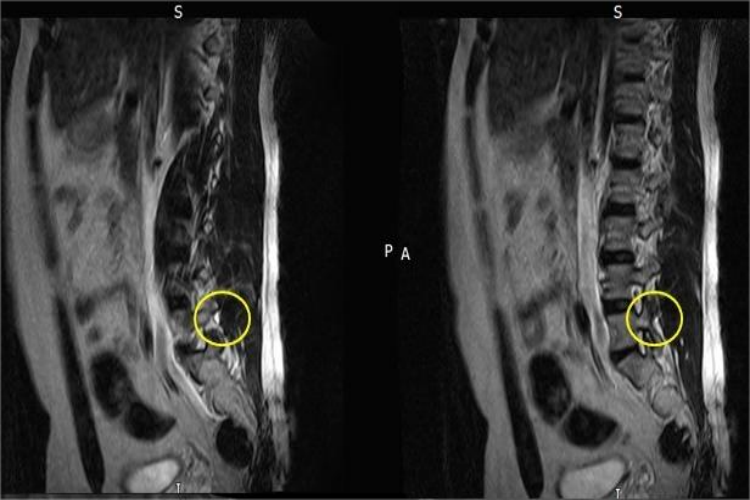

腰椎小关节紊乱影像学检查可见关节突增生,关节间隙增宽、对合不良,关节突关节退变,软骨下硬化,关节内碎骨、积液、积气等改变。同时患者还可伴有腰部疼痛,或牵扯到骶尾部、臀部疼痛,无下肢放射痛。腰椎关节突关节部位有明显压痛,但无向下的放射痛。